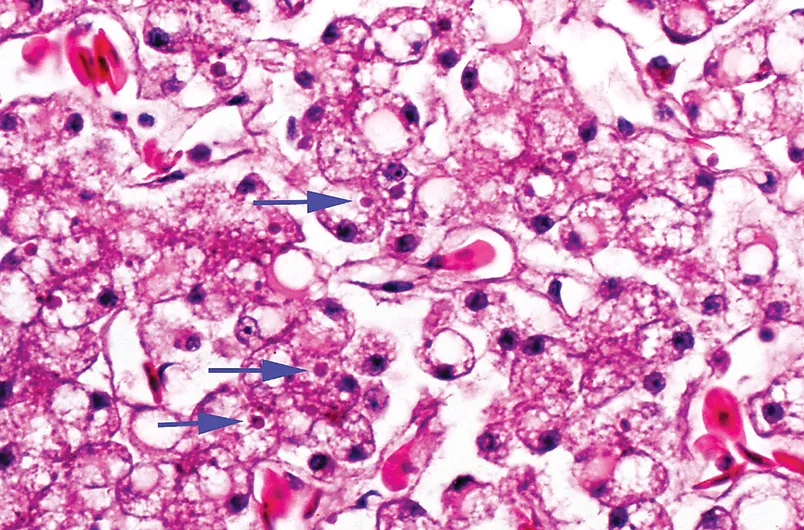

Figure 1 Argentine boa (Boa constrictor occidentalis) with boid inclusion body disease viral infection. This patient was presented for intermittent anorexia and diarrhea, weight loss, and a recurrent respiratory condition.

Nineteen percent of snakes were positive for nucleoprotein; 41.5% of those were boa constrictors, of which 87% were subclinically affected. The remainder showed clinical signs indicating chronic illnesses, but none had indications of CNS disease, often considered the hallmark of boid inclusion body disease.2